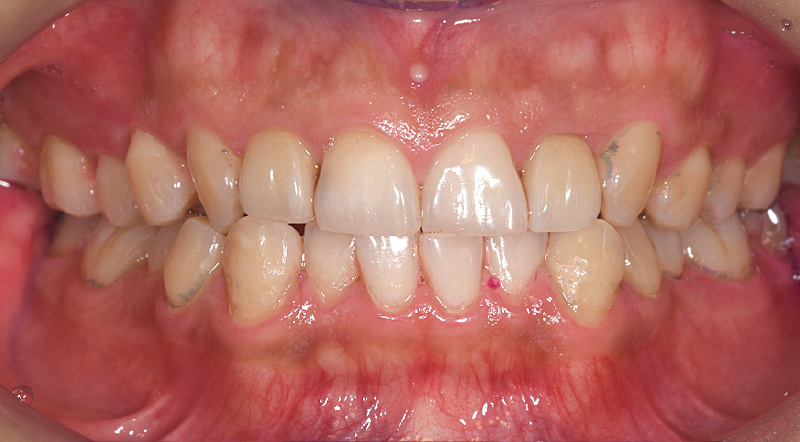

●症例2:30代男性

ソニッケアーの旧製品を自己流で使用。ゴシゴシと大きく動かしながら磨いていたため、「ソニッケアー6100」の導入を機に、ブラシを手磨きの感覚で動かさないことや正しい角度を鏡を見ながら丁寧に指導。2週間後には磨き残しが減るなど、改善傾向が認められました。

![[写真] 初診時の染め出しの状態](/academic/dentalmagazine/wp-content/uploads/sites/2/2026/04//196-12_photo07.jpg)

症例2-1 初診時の染め出しの状態。ソニッケアー旧製品を自己流で動かしながら磨いていた。 -

![[写真] 初診から2週間後の染め出しの状態](/academic/dentalmagazine/wp-content/uploads/sites/2/2026/04//196-12_photo09.jpg)

症例2-3 初診から2週間後の染め出しの状態。前歯部にはプラークが残存しているが、全体的には改善傾向が見られるようになってきた。